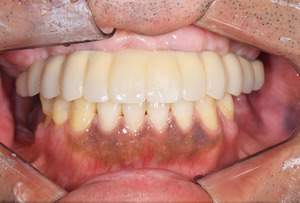

| 年齢・性別 | 63歳・男性 |

|---|---|

| 主訴 | インプラントがしたい |

| 治療内容 | オールオン4(上顎) |

| 治療費 | オペ料金(仮歯・薬代金含み)150万円+上部構造 (ハイブリットセラミック)150万円=計300万円(消費税別) |

| 治療期間 | 7ヶ月 |

| リスク・副作用 | 治療後の口腔管理が不適切な場合、インプラント周囲に炎症が生じインプラントが脱落する恐れがある。 |

審美的にも、機能的にも調和がとれており何よりも食べ物がちゃんとかめると言う事に感激されておりました。

今後定期検診をしながら経過を診て行きたいと思い

ます。